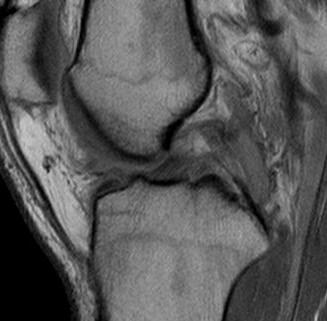

Arthroscopy

May miss tear as is extra-synovial

Chronic PCL tear from femur

Acute PCL femoral avulsion

Apparent ACL laxity due to PCL tear and posterior tibial sag; ACL tension restored with anterior drawer